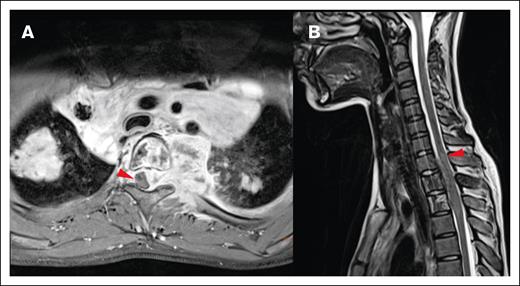

Local impact on CNS structures. (A) Displacement and mild compression of spinal cord to the right without contrast enhancement in the transverse T1 fat saturated image. (B) The same patient with edema clearly visible in the spinal cord in a sagittal T2-weighted MRI image.

Most lesions (92.7%) extended through the neural foramina of either the vertebrae or sacral bone; 2 lesions did not extend through the neural foramina, and 2 lesions could not be evaluated (Figure 4). Thirty-one lesions entered the spinal canal. Of these, 54.8% caused displacement of the spinal cord, 25.8% were adjacent to the spinal cord but did not cause displacement, and 19.4% did not contact the spinal cord (Figure 5). None of the lesions infiltrated into the spinal cord itself. Spinal cord edema was evaluated for patients who had MRI available (17 of 31 lesions). Among these evaluable lesions, only 12.9% had evidence of spinal cord edema.